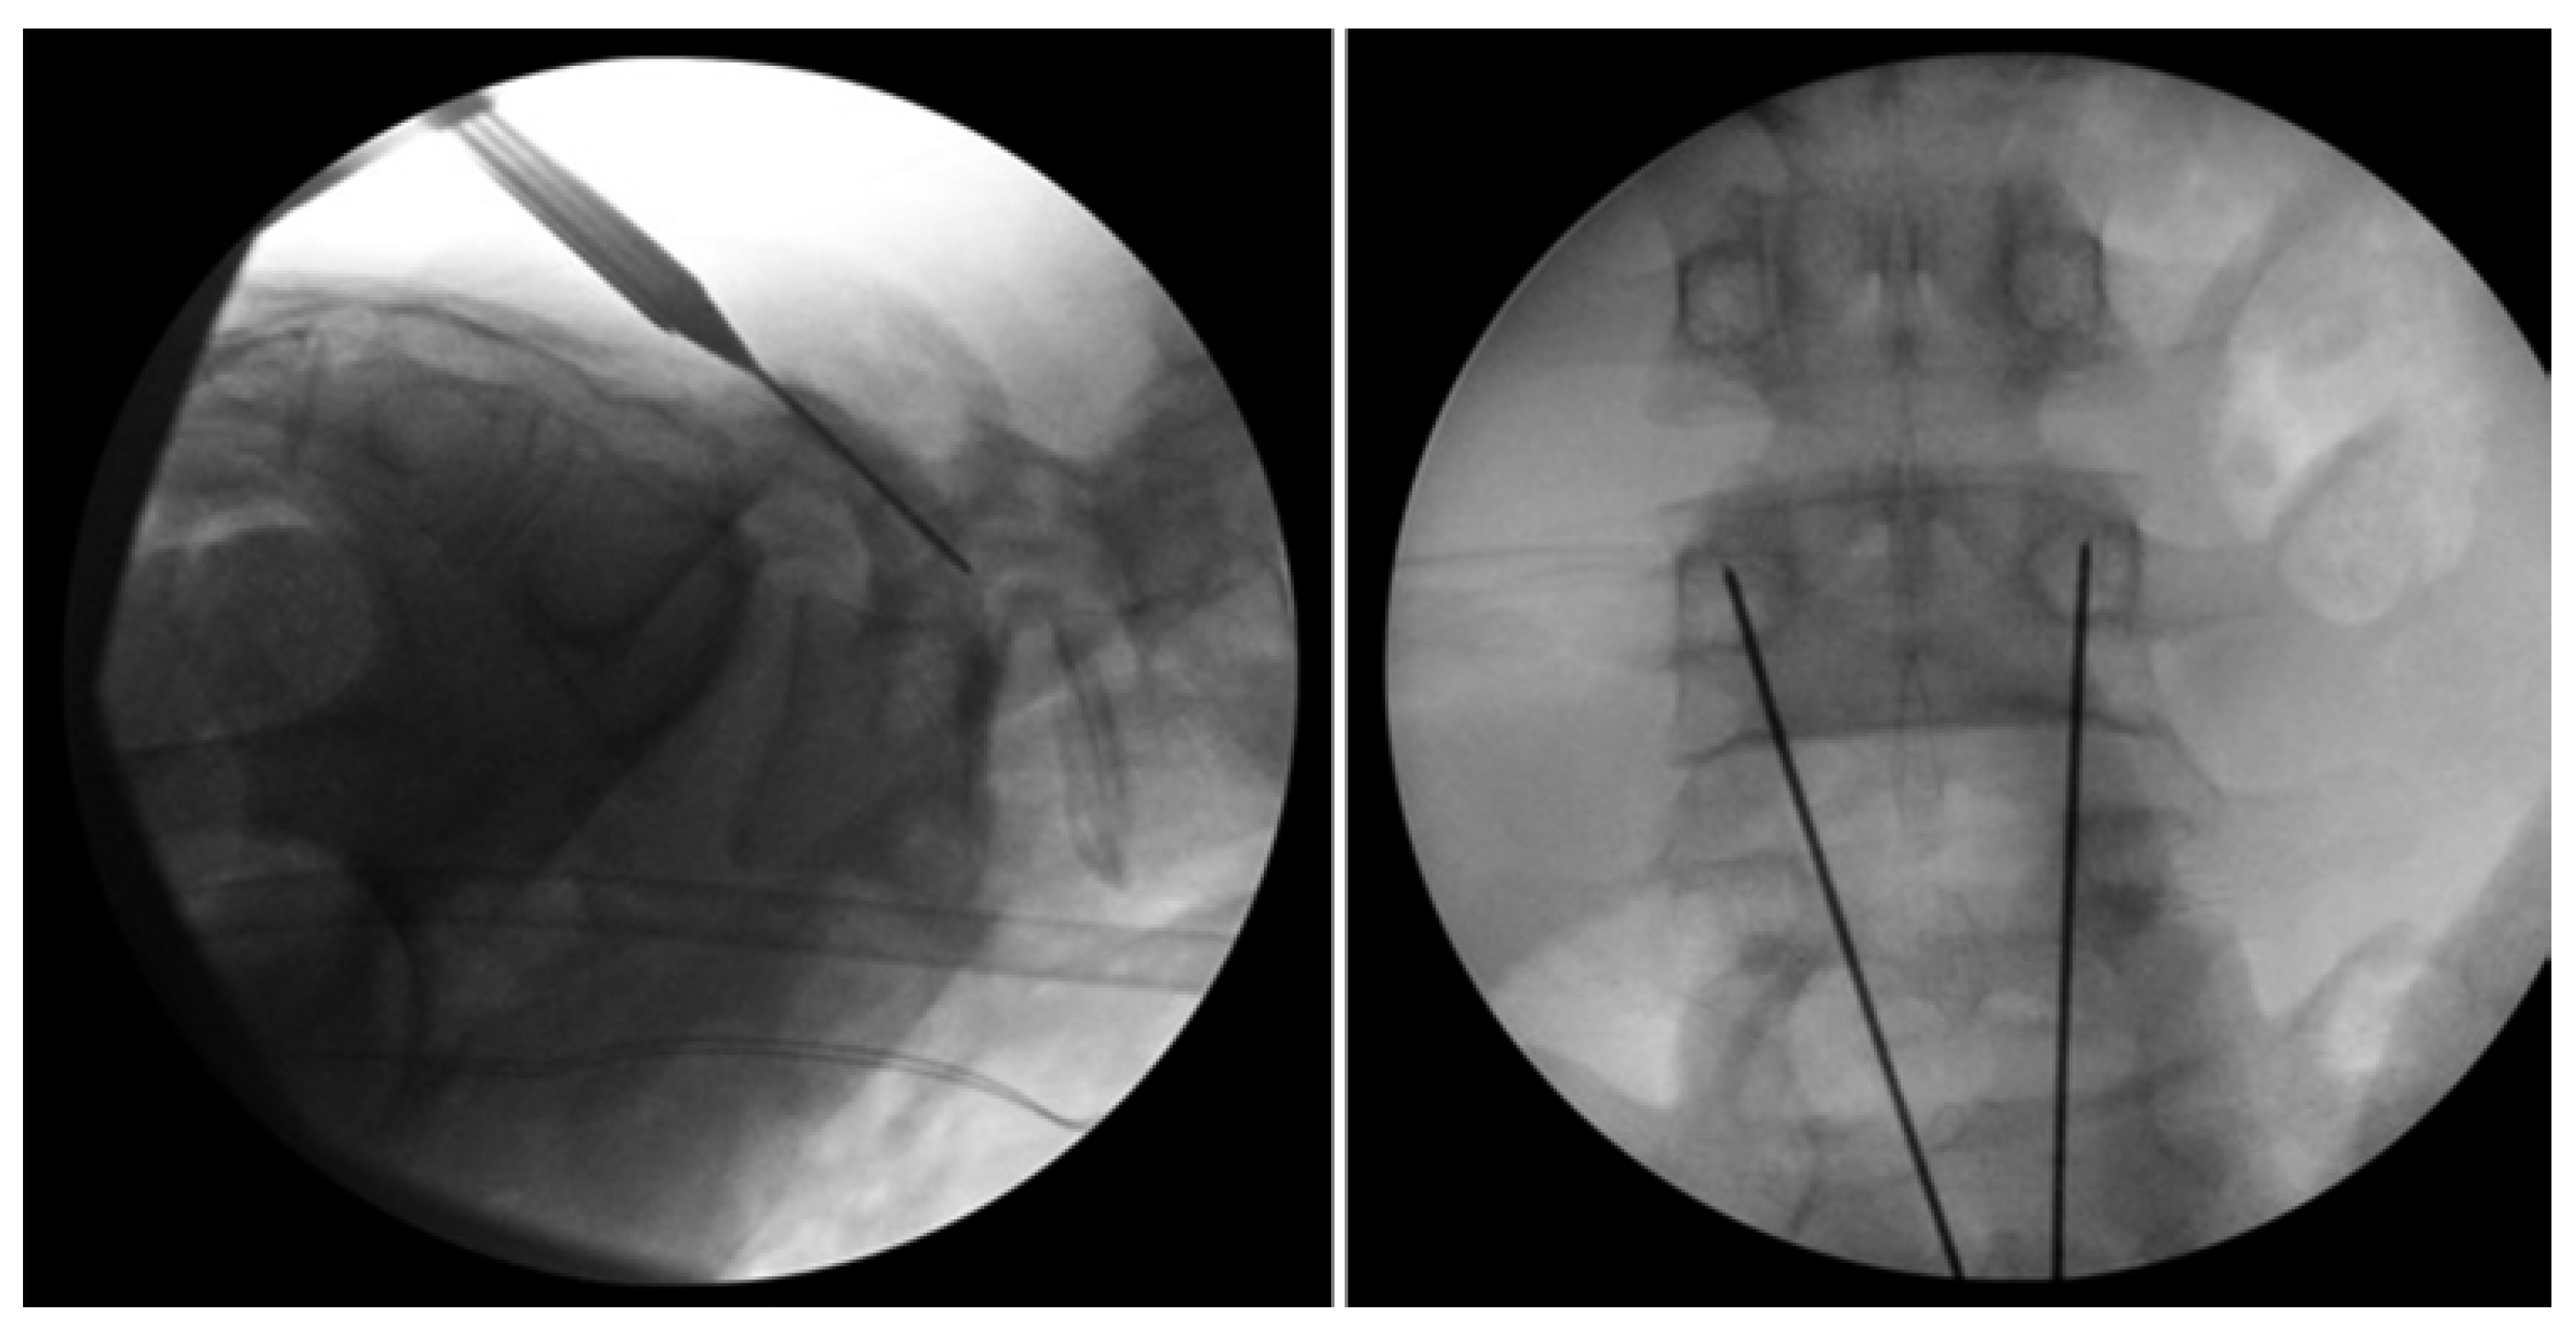

Levi Technique—Minimally Invasive Direct Pars Screw Placement

- Widi, G.A.; Williams, S.K.; Levi, A.D. Minimally invasive direct repair of bilateral lumbar spine pars defects in athletes. Case Rep. Med. 2013, 2013, 659078. [Google Scholar] [CrossRef]

- Ghobrial, G.M.; Crandall, K.M.; Lau, A.; Williams, S.K.; Levi, A.D. Minimally invasive direct pars repair with cannulated screws and recombinant human bone morphogenetic protein: Case series and review of the literature. Neurosurg. Focus 2017, 43, E6. [Google Scholar] [CrossRef] [PubMed]